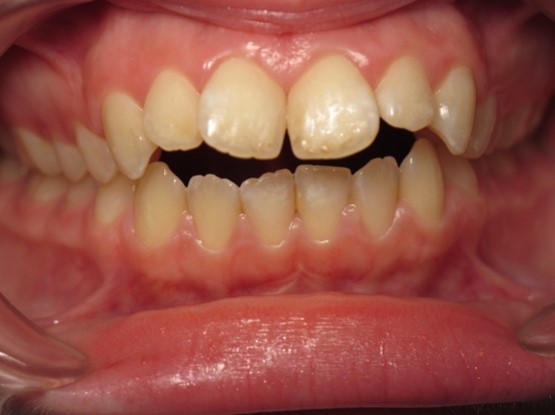

Pic.22. Tortoocclusion of teeth 11 and 21, open bite.

Pic.23. Tortoocclusion of teeth 11 and 21, prognathic, cross bite.